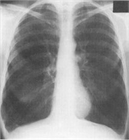

病態

1. 慢性閉塞性肺疾患(chronic obstructive pulmonary disease:COPD)は、タバコ煙を主とする有害物質を長期に吸入曝露することで生ずる肺の炎症性疾患であり、呼吸機能検査で正常に復することのない気流閉塞を示す。